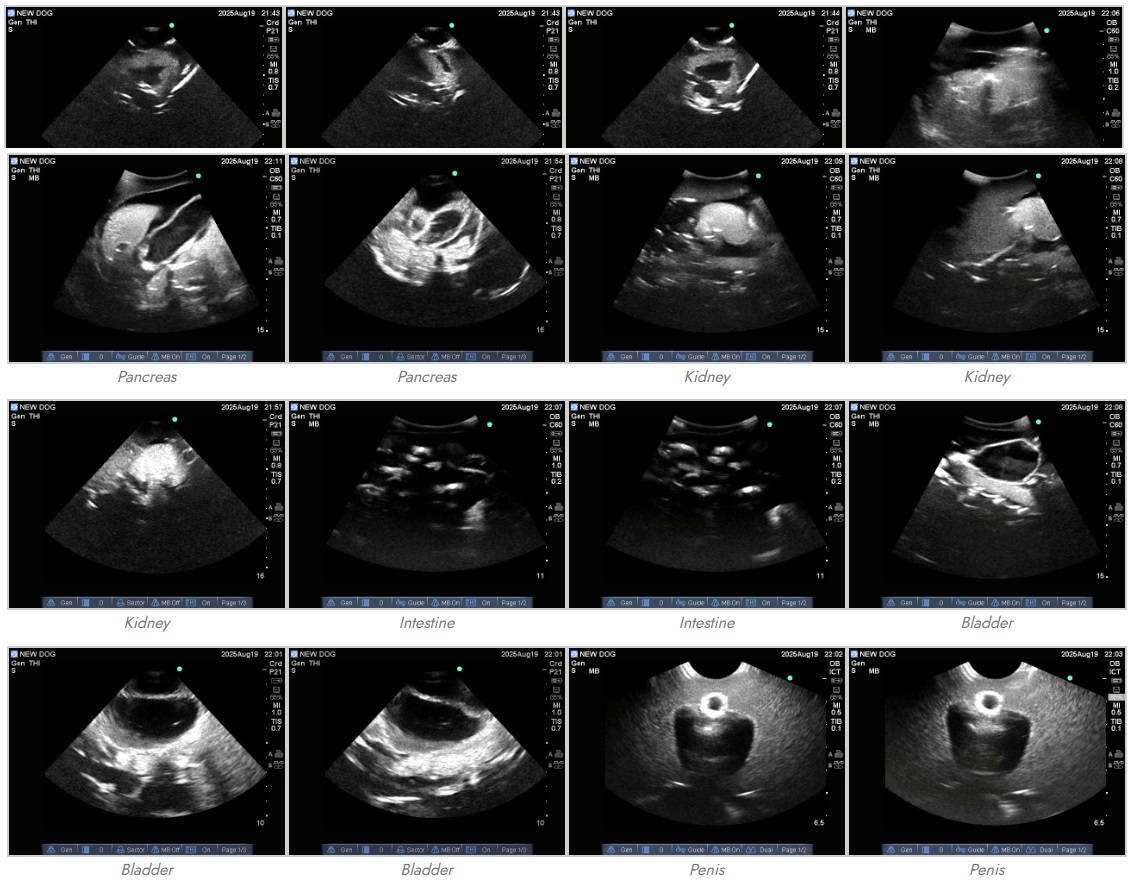

Dog (Canine) Phantom for X-Ray CT, US, MRI

![]() Dog/Canine PhantomÀº ¼öÀÇÇÐ ±³À° ÇöÀåÀÇ ½ÇÁúÀûÀÎ ¿ä±¸¿Í ½Ç¹« ÀÓ»ó ÈÆ·ÃÀ» ÃæÁ·Çϱâ À§ÇØ ¼¼½ÉÇÏ°Ô ¼³°èµÇ¾ú½À´Ï´Ù. ƯÈ÷ ¿¢½º·¹ÀÌ ÃÔ¿µ À§Ä¡ ¼±Á¤ ½Ç½ÀÀ» À§ÇØ °³¼±µÈ °üÀý ¿¬°á ±¸Á¶¸¦ äÅÃÇÔÀ¸·Î½á, ÀÌÀü ¸ðµ¨ ´ëºñ ºñ¾àÀûÀÎ ¹ßÀüÀ» ÀÌ·ç¾î³Â½À´Ï´Ù. ÀÌ ¸ðµ¨ÀÇ ÇØºÎÇÐÀû ¼³°è´Â ºÒ ¸¶½ºÆ¼ÇÁ¿Í ·ÎµðÁö¾È ¸®Áö¹é ¹Í½º°ß(¼öÄÆ)ÀÇ ½ÇÁ¦ CT µ¥ÀÌÅͼÂÀ» ±â¹ÝÀ¸·Î Á¦À۵Ǿî, µ¶º¸ÀûÀÎ ÇØºÎÇÐÀû »ç½Ç¼ºÀ» º¸ÀåÇÕ´Ï´Ù. ¶ÇÇÑ, ÃÖ÷´Ü AI ±â¼ú°ú °íµµÈµÈ ¾Ë°í¸®ÁòÀ» Ȱ¿ëÇÏ¿© ¸Å¿ì º¹ÀâÇϰí Á¤¹ÐÇÑ ÇØºÎÇÐÀû ±¸Á¶¸¦ ÃßÃâÇϰí, À̸¦ °æÀÌ·Î¿î ¼öÁØÀÇ Á¤È®µµ·Î ÀçÇöÇØ ³Â½À´Ï´Ù. 🐕 Â÷¼¼´ë °ßü ÆÒÅÒ (Canine Phantom): ¼öÀÇÇÐ ±³À° ¹× ¿¬±¸ÀÇ »õ·Î¿î ±âÁØ ¼öÀÇÇÐ ±³À°, ¿¬±¸ ¹× ÀÓ»ó ½Ç½ÀÀÇ °íµµÈµÈ ¿ä±¸»çÇ×À» ÃæÁ·Çϱâ À§ÇØ ¼³°èµÈ À̹ø ÃֽŠCanine PhantomÀº ÇØºÎÇÐÀû »ç½Ç¼º°ú ÈÆ·ÃÀÇ ´Ù°¢È Ãø¸é¿¡¼ »õ·Î¿î ÀÌÁ¤Ç¥¸¦ Á¦½ÃÇÕ´Ï´Ù. º» ¾÷±×·¹ÀÌµå ¸ðµ¨Àº ij³ª´Ù, ¹Ì±¹, ¿µ±¹, È£ÁÖÀÇ ÁÖ¿ä ¼öÀÇÇÐ ±â°üµé°úÀÇ Çù¾÷À» ÅëÇØ °³¹ßµÇ¾úÀ¸¸ç, Àü ¼¼°è Àü¹®°¡µéÀÇ Çǵå¹éÀ» ¹Ý¿µÇÏ¿© ÀÌÀü ¸ðµ¨º¸´Ù ´ëÆø Çâ»óµÈ ¼º´ÉÀ» ÀÚ¶ûÇÕ´Ï´Ù. 🔬 Á¤¹ÐÇÑ ¼³°è¿Í Çõ½ÅÀû ±â¼ú